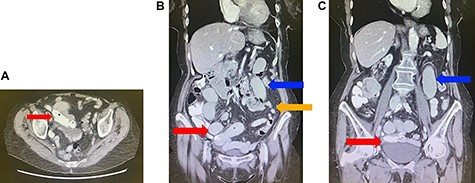

(A) Axial view of computed tomography (CT) of the abdomen demonstrating migration of the biliary stents into the small bowel (red arrow). (B) Coronal view of CT of the abdomen demonstrating migration of the biliary stents into the small bowel (red arrow), with dilated (blue arrow) and collapsed (orange arrow) loops of small bowel suggestive of a small bowel obstruction. (C) Coronal view of CT of the abdomen demonstrating migration of the biliary stents into the small bowel (red arrow) and dilated loops of small bowel (blue arrow).

A 90-year-old female presented to the hospital for small bowel obstruction requiring surgery. Six months prior, she underwent an endoscopic retrograde cholangiopancreatography (ERCP) with sphincterotomy and insertion of side-by-side straight plastic stents followed by a laparoscopic cholecystectomy for cholangitis secondary to choledocholithiasis. The stents were to be removed 6 weeks post cholecystectomy; however, the procedure was delayed for 5 months due to significant deconditioning requiring prolonged physical rehabilitation. During the repeat ERCP, there were concerns for a biliary mucosal tear resulting in prophylactic insertion of two covered metal biliary stents with two plastic biliary stents in situ. She had an unremarkable hospital admission and was sent home the following day. Two weeks after the repeat ERCP, she presented to the emergency department with colicky abdominal pain, distention and bilious vomiting. Abdominal examination demonstrated a markedly distended abdomen with periumbilical tenderness on palpation. An abdominal X-ray revealed projection of the biliary stents in the pelvis (Fig. 1), with an abdominal computed tomography scan confirming the migration of stents to the small bowel resulting in a small bowel obstruction (Fig. 2A–C). An emergency mini-laparotomy was performed revealing seropurulent ascites and palpable biliary stents obstructing the proximal ileum causing upstream dilatation. A small enterotomy was performed, all four stents were retrieved (Fig. 3A–C) and the enterotomy was closed with interrupted full-thickness repair using 4.0 polydioxanone sutures. The patient had a slow progression due to prolonged ileus and was discharged from the hospital after 2 weeks.